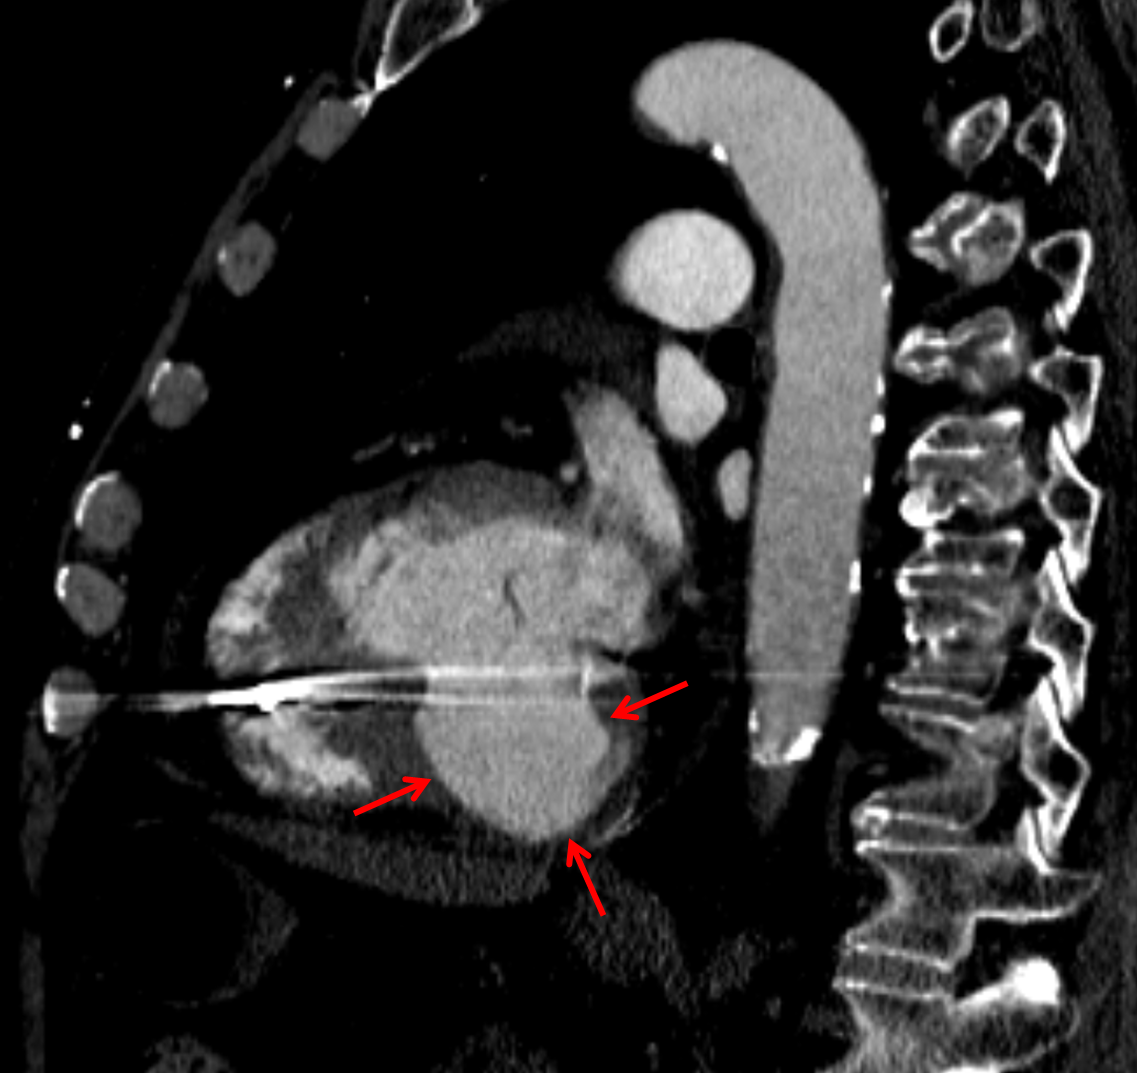

Left ventricular pseudoaneurysm arising from the basal inferior wall with peripheral thrombus and mural calcification. Recommend correlation with any available prior imaging to document stability. Further imaging followup can be dictated by outpatient cardiology referral.